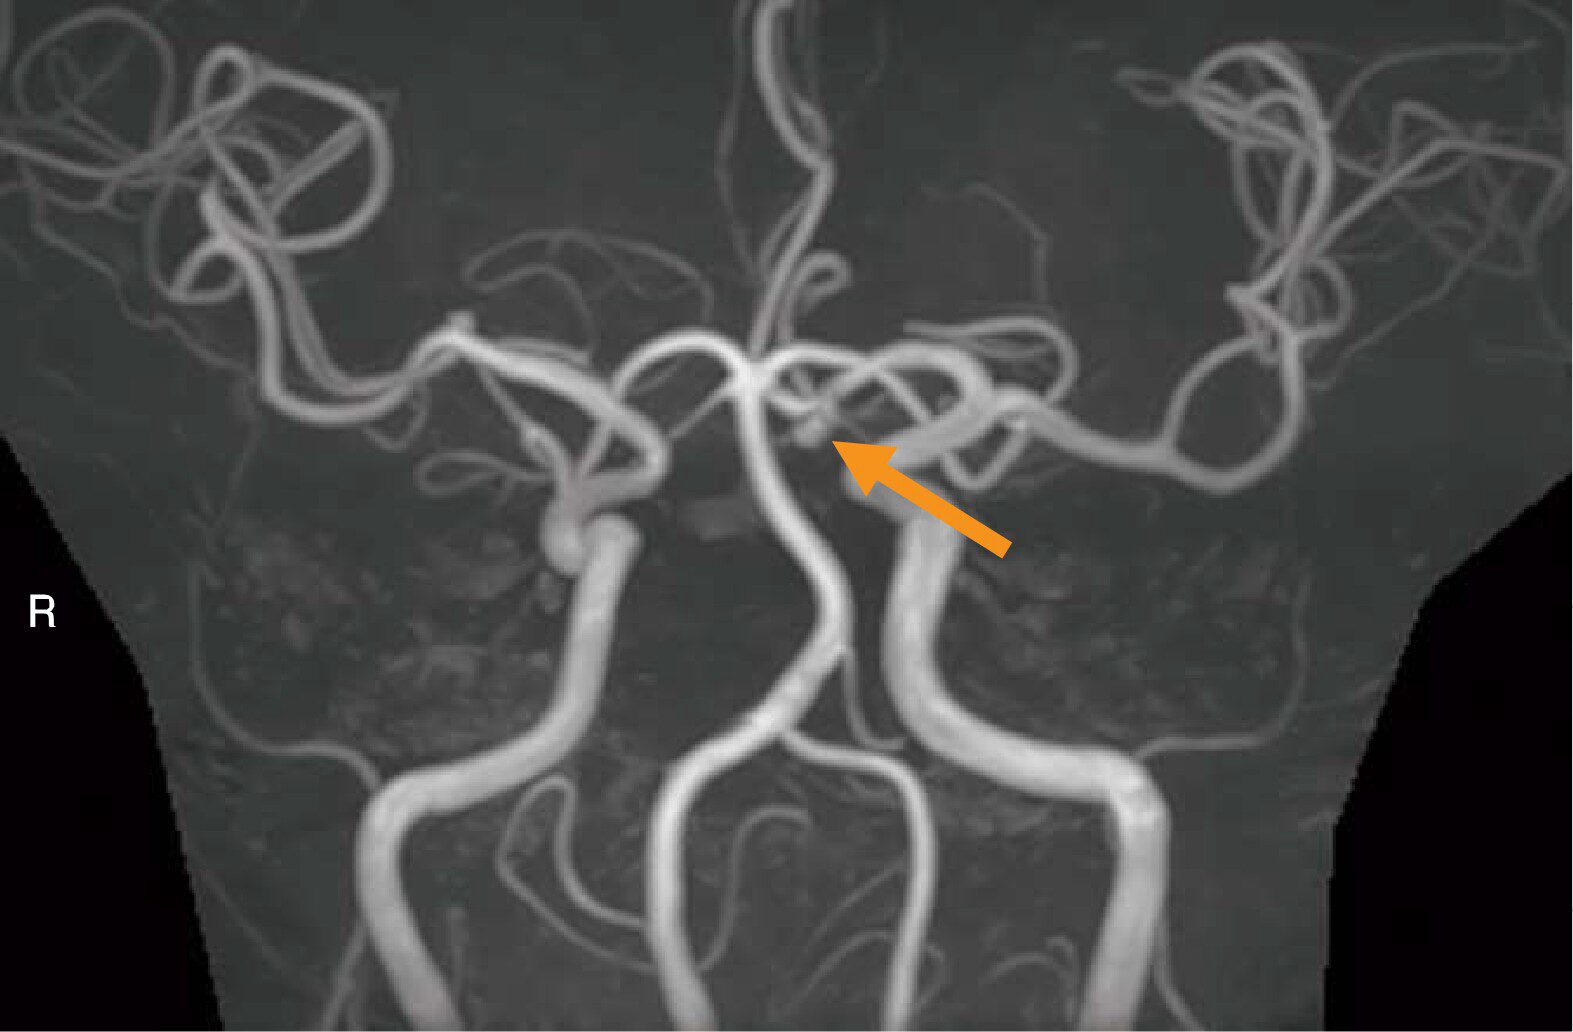

Q8 / 20医用画像撮影技術学

頭部MRAのMIP像(別冊No.3A)及び3D再構成像(別冊No.3B)を別に示す。矢印で示す動脈瘤の部位はどれか。

- 1脳底動脈

- 2後交通動脈

- 3後大脳動脈

- 4前交通動脈

- 5中大脳動脈